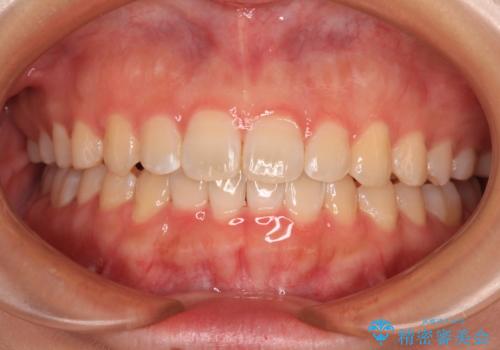

[ マウスピース矯正 ] 出っ歯に見える前歯を改善したい

![[ マウスピース矯正 ] 出っ歯に見える前歯を改善したいの症例 治療前](https://seimitsushinbi.jp/wp/wp-content/uploads/2023/10/IMG_6858-500x350.jpg?v=1697014973)

![[ マウスピース矯正 ] 出っ歯に見える前歯を改善したいの症例 治療後](https://seimitsushinbi.jp/wp/wp-content/uploads/2023/10/8a6c9bf89570c0c75da0a5fabd1cd70e-500x350.jpg?v=1697014858)